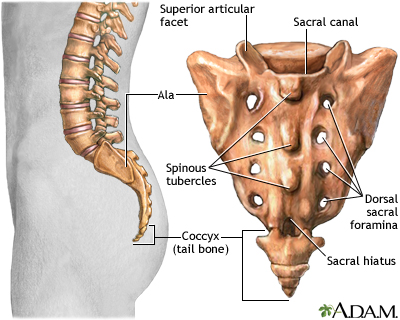

A lumbosacral spine x-ray is a picture of the bones (vertebrae) in the lower part of the spine. This area includes the lumbar region and the sacrum, the area that connects the spine to the pelvis.